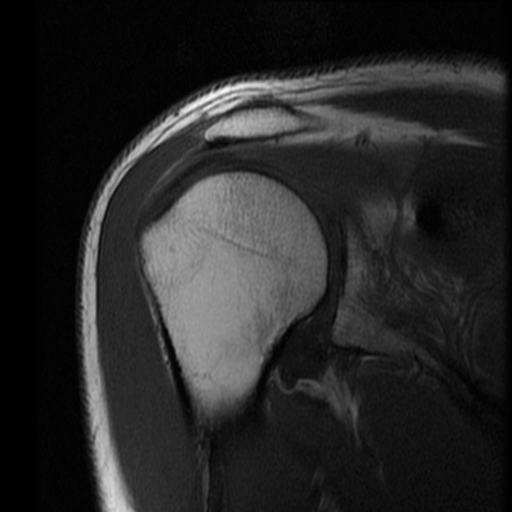

Oh, yeah, and by the time I got home that evening, I couldn't raise my right arm. After a couple of months, I still had reduced ROM  so I got a referral to an orthopedist. She looked at the x-ray and pronounced a "contusion of the deltoid - Leave it alone and call me if it doesn't get better".  Come June, it still wasn't right so I got scheduled for an MRI (6 weeks later!).

After more consultation with the orthopedist, I'm starting physical therapy next week to deal with the last little "pinches".  She said there was no tearing and only a small bone spur. If PT doesn't work, cortisone is the next step. After that, we either start cutting, or we chalk it up to old age. (ouch! Now that hurt)

This is just 6 of one series of images. There were 12 series. In all, 130 images, each with millimeter resolution. Pretty cool.

Notice the poor marbling and high proportion of connectives. I recommend braising.